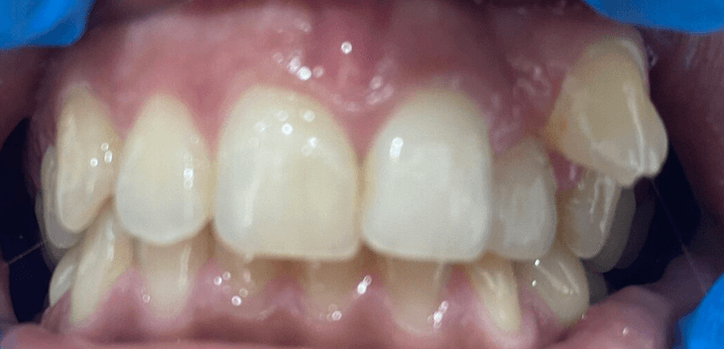

bone loss.jpg

Leaving broken teeth in the mouth can lead to severe complications when left untreated.